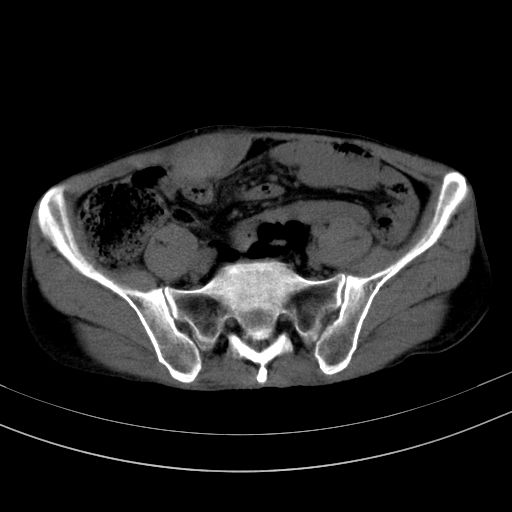

以下是引用37度在2010-1-9 14:37:00的发言:[br]1.双肾囊肿,左肾积水结石,.胆总管轻度扩张;[br]2.病灶在腹膜外,考虑纤维瘤。

以下是引用dyqct在2010-1-9 17:56:00的发言:[br]考虑:1.双肾囊肿,左肾积水结石、旋转不良。[br] 2.右侧腹直肌血肿或纤维瘤。[br]肠道准备不好。做个增强。